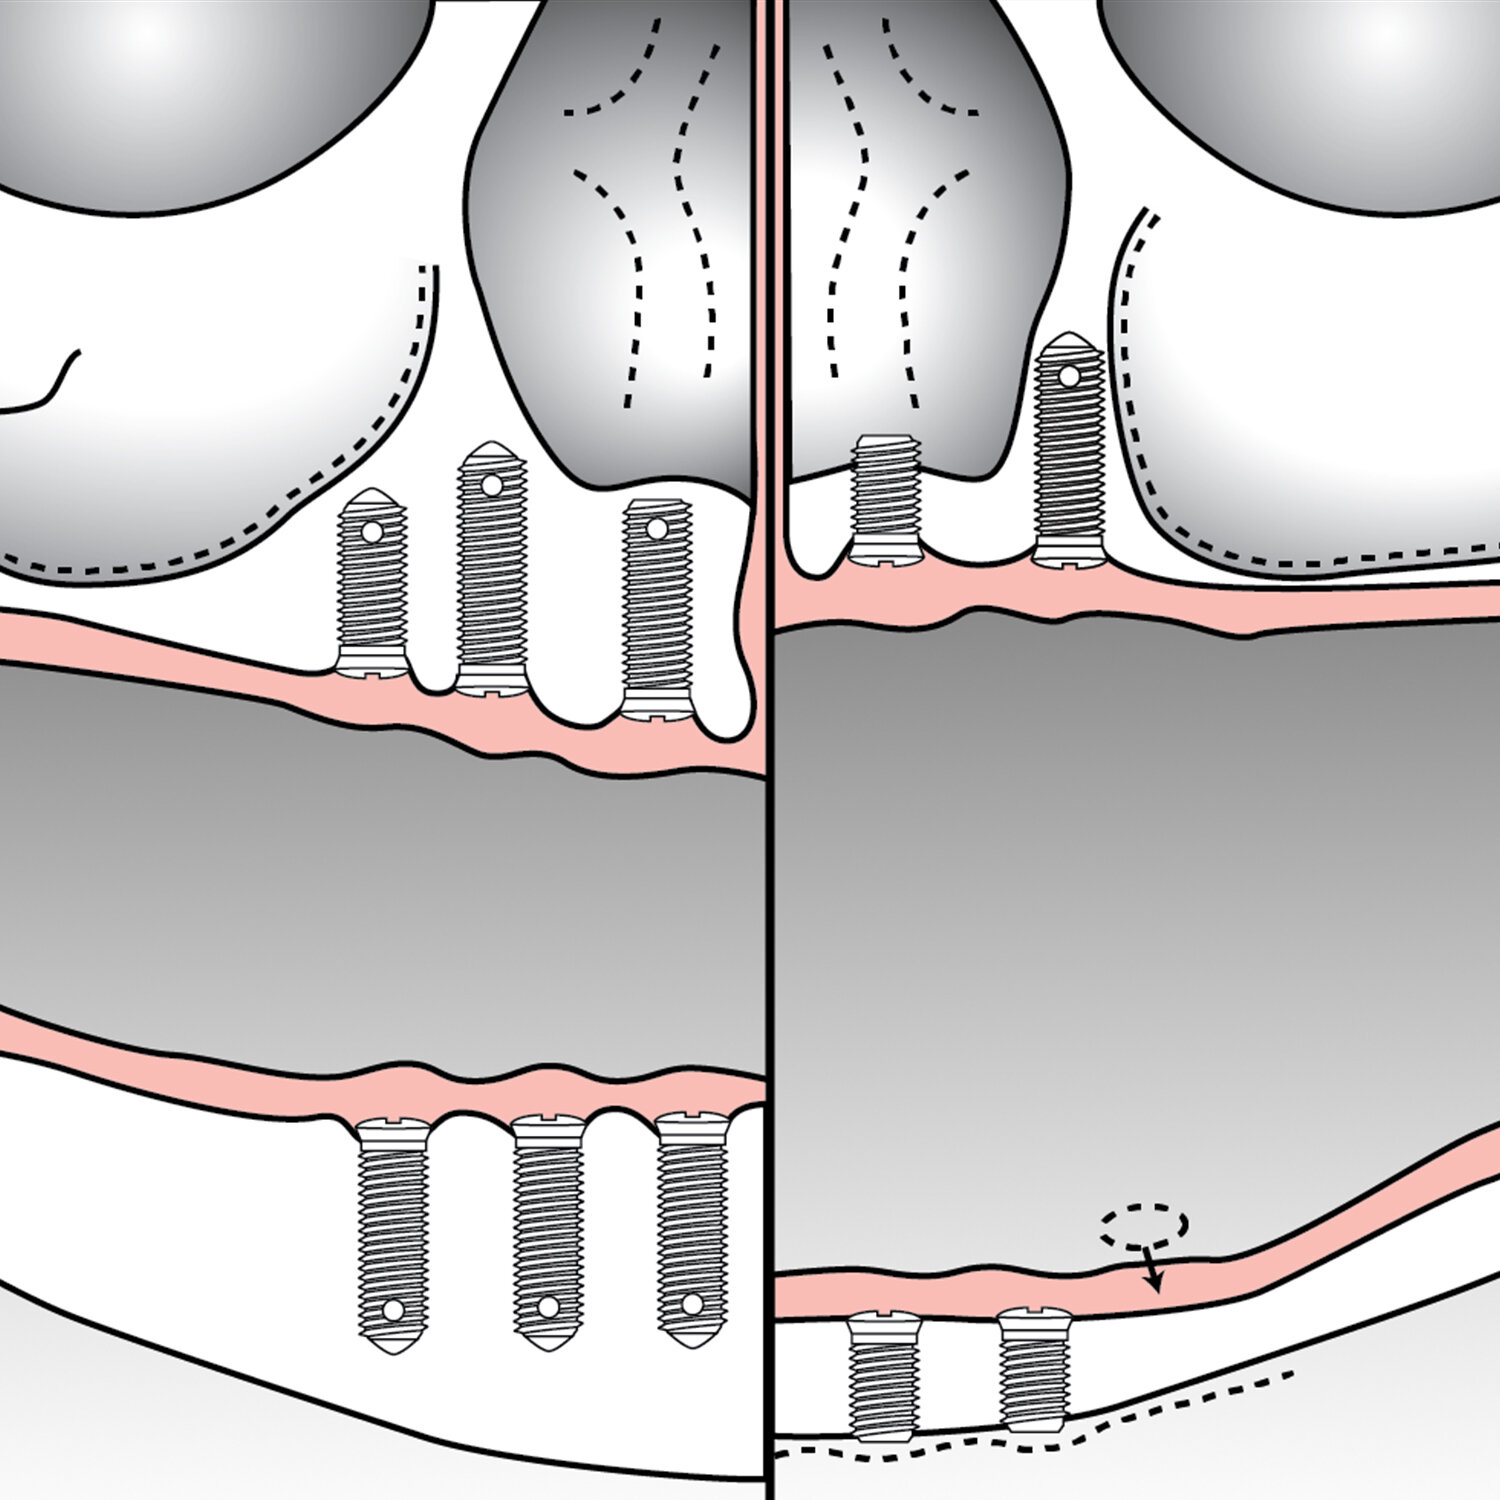

![Pedicle screw and bar placement for spinal fusion (Copy)]()

Pedicle screw and bar placement for spinal fusion (Copy)